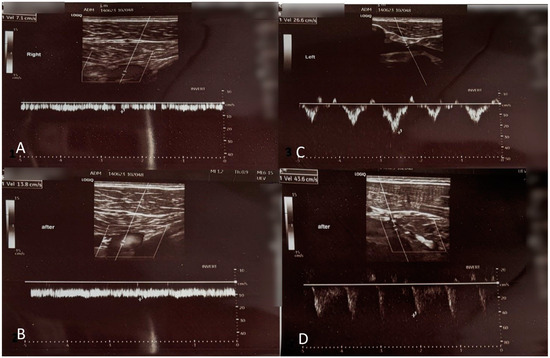

2. Case Presentation